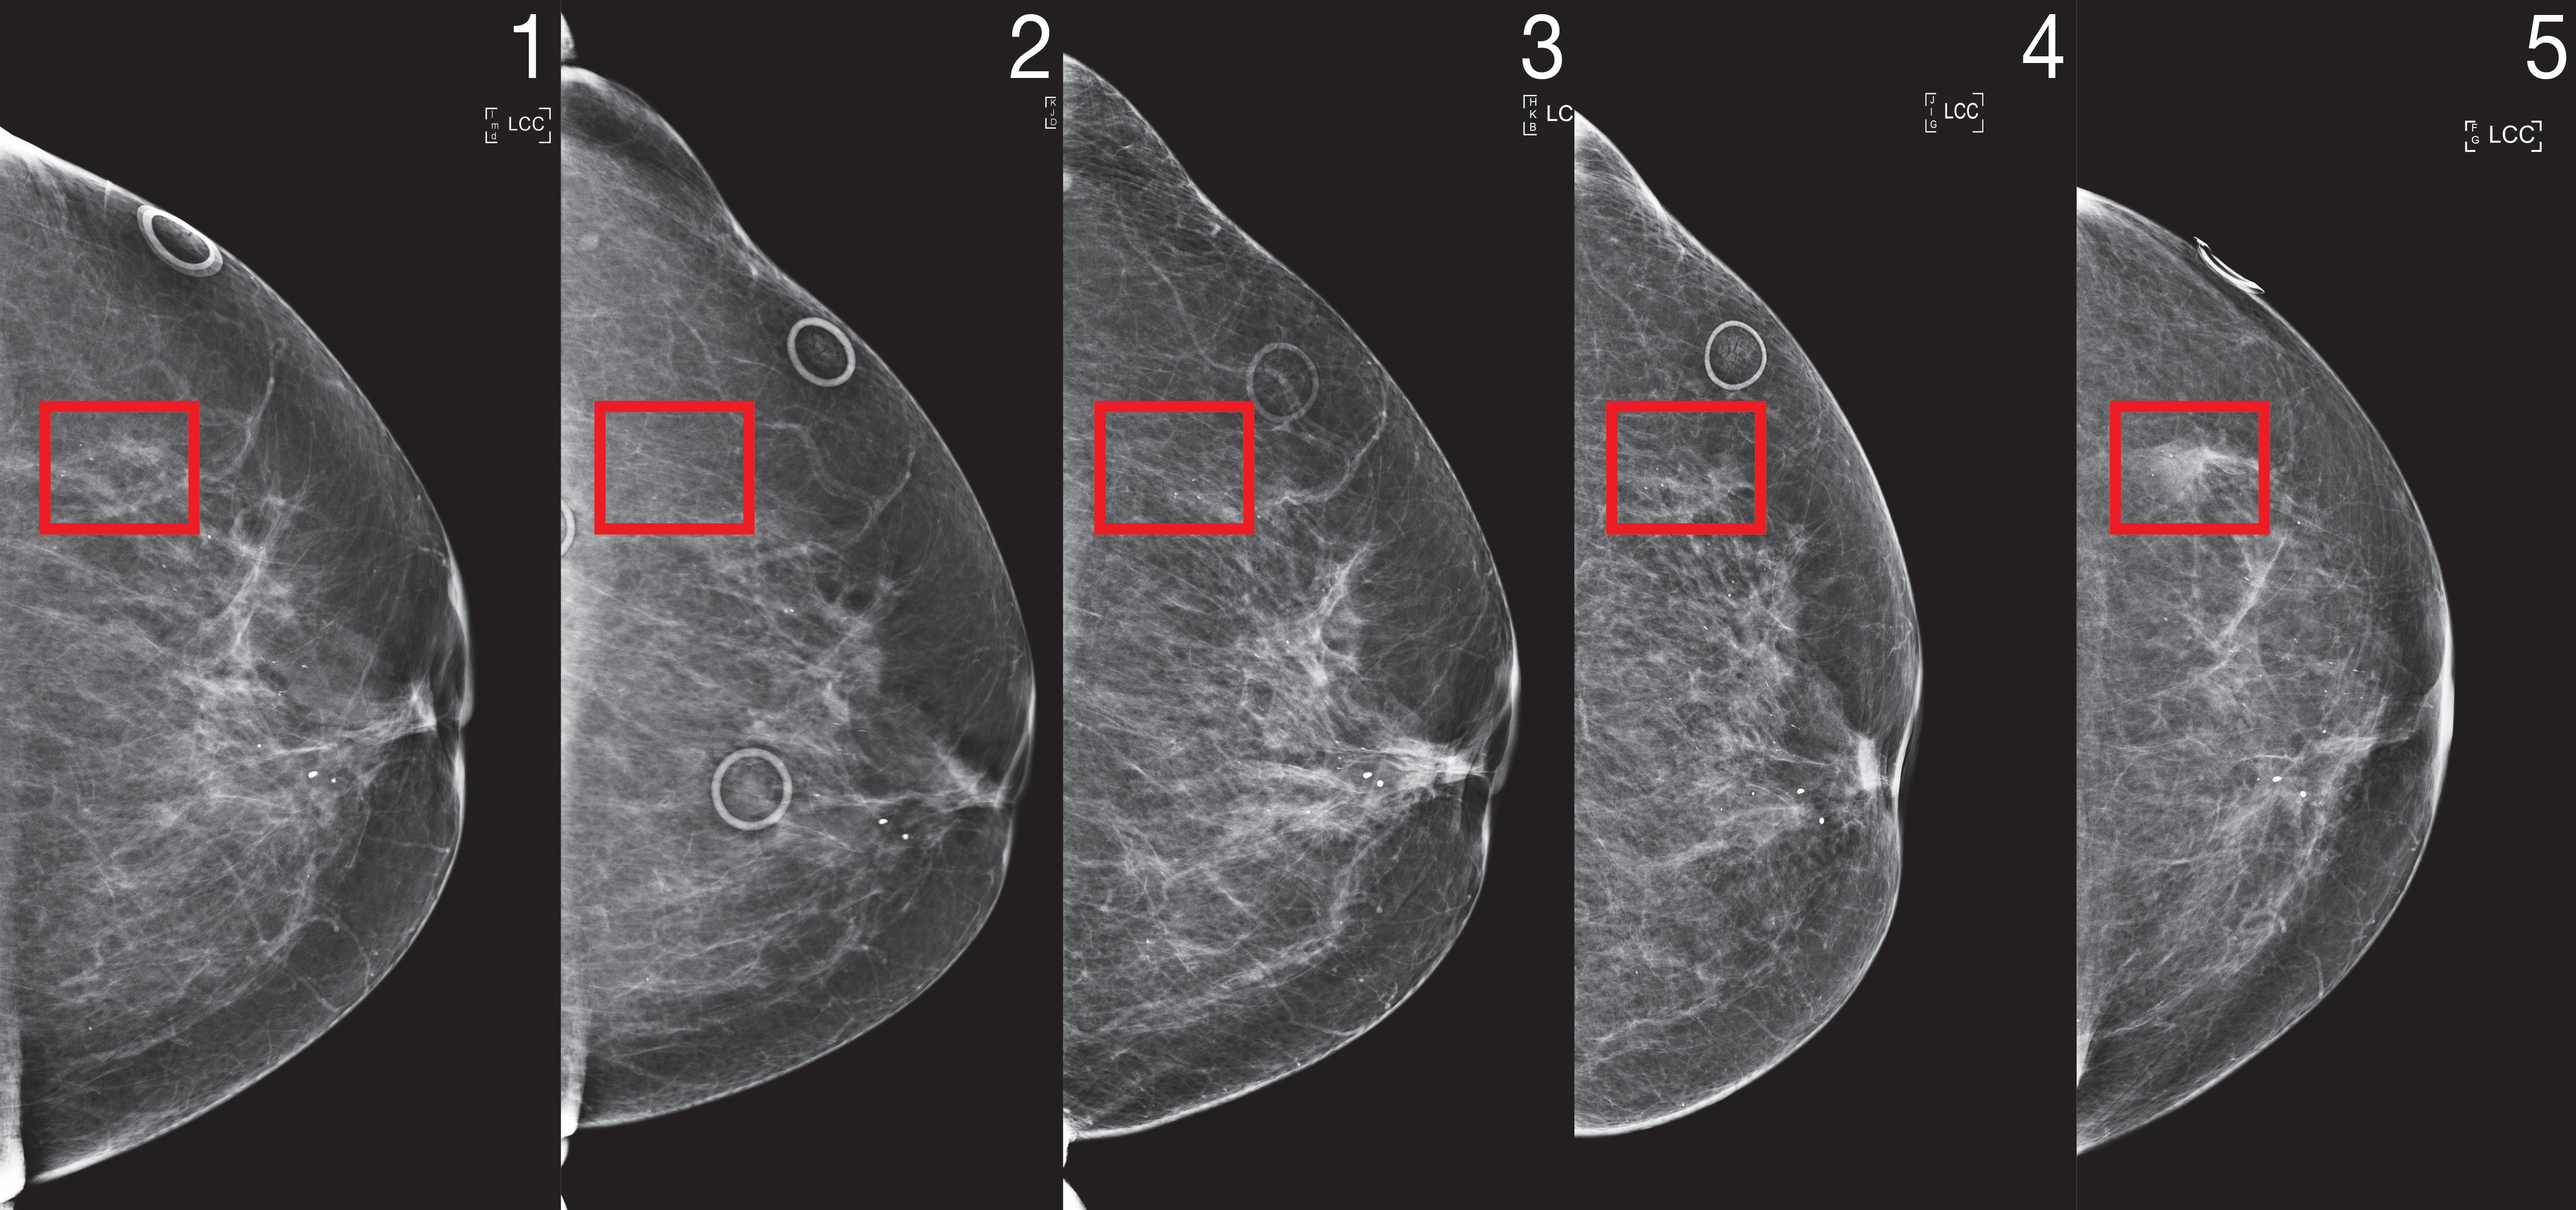

To that end, they tailored their new “Mirai” algorithm to capture the unique requirements of risk modeling. Mirai jointly models a patient’s risk across multiple future time points, and can optionally benefit from clinical risk factors such as age or family history, if they are available. The algorithm is also designed to produce predictions that are consistent across minor variances in clinical environments, like the choice of mammography machine.

The team trained Mirai on the same dataset of over 200,000 exams from Massachusetts General Hospital (MGH) from their prior work, and validated it on test sets from MGH, the Karolinska Institute in Sweden, and Chang Gung Memorial Hospital in Taiwan. Mirai is now installed at MGH, and the team’s collaborators are actively working on integrating the model into care.

Mirai was significantly more accurate than prior methods in predicting cancer risk and identifying high risk groups across all three datasets. When comparing high risk cohorts on the MGH test set, the team found that their model identified nearly two times more future cancer diagnoses compared the current clinical standard, the Tyrer-Cuzick model. Mirai was similarly accurate across patients of different races, age groups, and breast density categories in the MGH test set, and across different cancer subtypes in the Karolinska test set.

CONSISTENT PERFORMANCE ACROSS CLINICAL ENVIRONMENTS

To incorporate deep-learning risk models into clinical guidelines, the models must perform consistently across diverse clinical environments, and its predictions cannot be affected by minor variations like which machine the mammogram was taken on. Even across a single hospital, the scientists found that standard training did not produce consistent predictions before and after a change in mammography machines, as the algorithm could learn to rely on different cues specific to the environment. To de-bias the model, the team used an adversarial scheme where the model specifically learns mammogram representations that are invariant to the source clinical environment, to produce consistent predictions.

To further test these updates across diverse clinical settings, the scientists evaluated Mirai on new test sets from Karolinska in Sweden and Chang Gung Memorial Hospital in Taiwan, and found it obtained consistent performance. The team also analyzed the model’s performance across races, ages, and breast density categories in the MGH test set, and across cancer subtypes on the Karolinska dataset, and found it performed similarly across all subgroups.